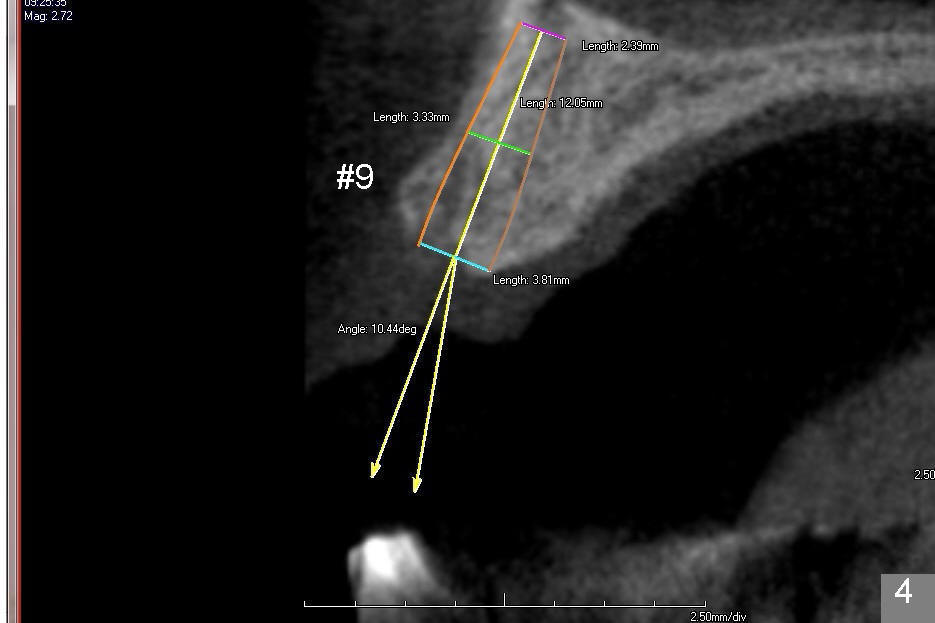

The second design is to place relatively smaller implants with the occlusion in mind (Fig.3,4). The starting point for the osteotomy will be as lingual as possible (especially Fig.4). The axis of the implant will be more parallel to the buccal plate. The angles of the angled abutments will be less (Fig.1 vs. 3; Fig.2 vs. 4). The cosmetic result may be better.

For the best trajectory, osteotomy at #8 should be initiated as palatally as possible (Fig.8 *). When a 4x11 mm 2-piece implant is placed, there is possibility that the apical buccal plate may be perforated (>). In contrast, a 3x11 mm 1-piece implant is more skinny with less coronal palatal thread exposure (Fig.9). The latter will be covered with bone graft and collagen dressing.